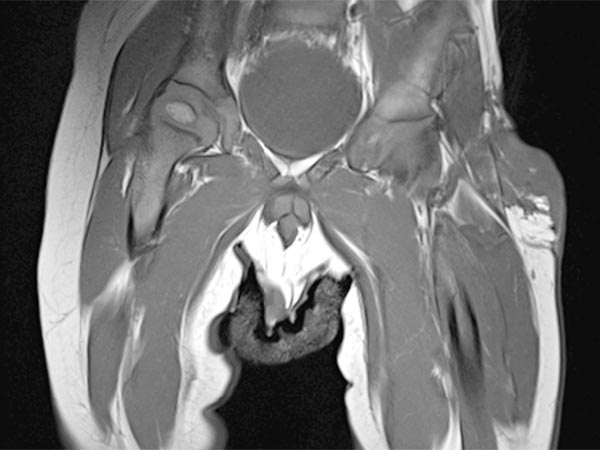

Axial, T2-weighted, fat-suppressed MRI of the patient at 7 years and 10 months of age.

The NICH is still visible under the skin as a hyperintense (white) flat structure, but significantly smaller than before embolization.